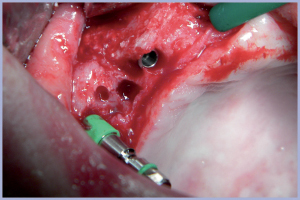

A Giugno 2011 si esegue l’intervento di implantologia sulla paziente. L’intervento segue quasi fedelmente quanto simulato sulla replica in resina: sul lato destro, una volta rimosse le viti di osteosintesi e verificata la stabilità dell’osso innestato si posizionano 3 impianti Exacone® Max Stability Ø 3,75 e, sul lato sinistro, senza rimuovere le viti di osteosintesi in quanto non interferiscono con l’inserimento degli impianti, si posizionano altri 3 impianti Exacone® Max Stability Ø 3,75.

Sono stati inseriti 6 impianti Exacone® Max Stability perché grazie al loro macrodesign e in particolare al profilo aggressivo delle spire incrementali permettono di raggiungere un’ottima stabilità primaria anche in osso di scarsa qualità (Figg. 25-39).